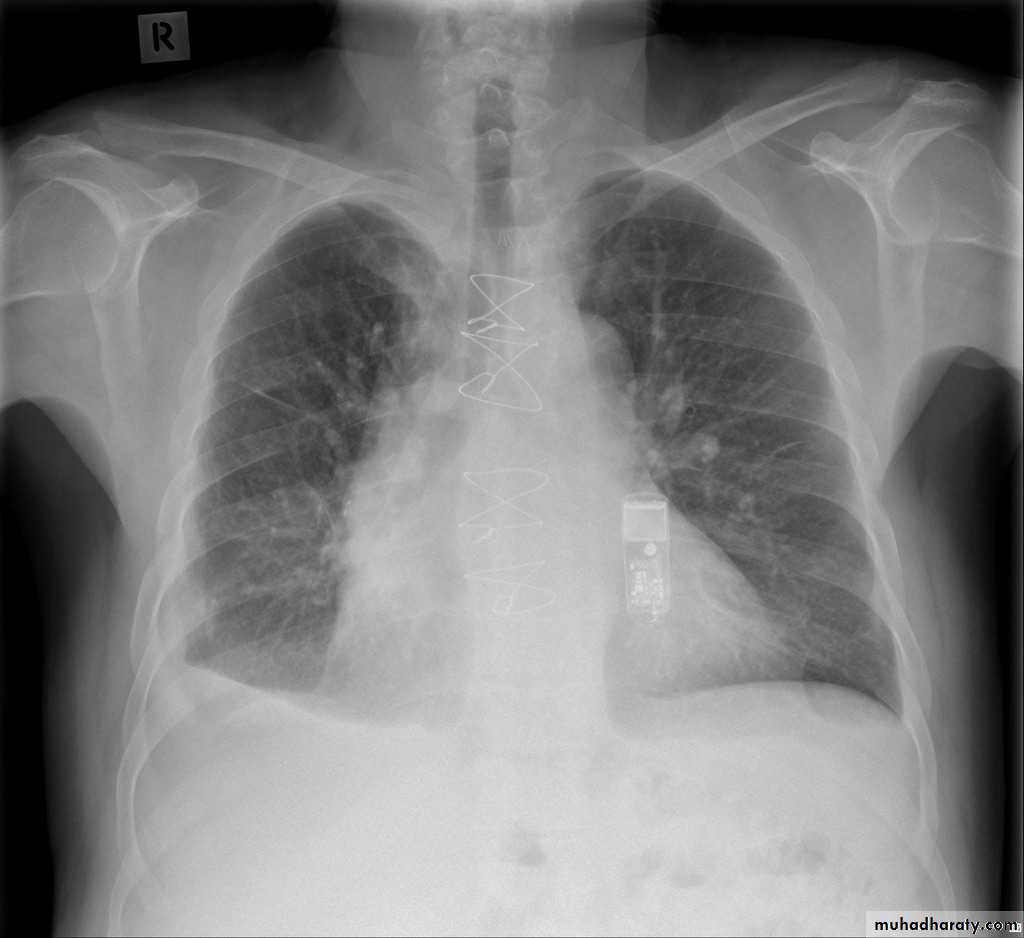

TOTAL LUNG CONSOLIDATION

Bronchopneumonia

Bronchopneumonia (also sometimes known as lobular pneumonia 1) is a radiological pattern associated with suppurative peribronchiolar inflammation and subsequent patchy consolidation of one or more secondary lobules of a lung in response to a bacterial pneumonia.Broncho pneumonia